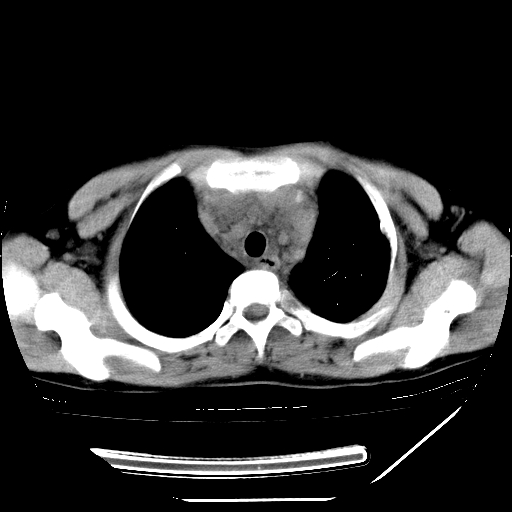

男,13岁,咳嗽、咳痰伴发热一周。

上纵隔课件多枚淋巴结,部分相互融合,左侧支气管壁增厚,肺纹理较右侧增粗,患者,男,13岁,

中上纵隔见多枚淋巴结肿大,部分相互融合成团片,左肺门增大,上叶支气管变窄,肺内多处斑片状 索条状及棉絮状致密影。临床“男,13岁,咳嗽、咳痰伴发热一周。”首先考虑:原发综合征!不除外淋巴瘤可能!

纵隔多发肿大淋巴结,部份有融合改变。双肺血管气管束增厚,以肺门为中心向外周散发,以左肺下叶为明显。考虑淋巴瘤可能性大。不除外原发综合征。

中上纵隔见多枚淋巴结肿大,部分相互融合成团片,左肺门增大,上叶支气管变窄,左肺支气管血管束增粗,可见磨玻璃样影。临床“男,13岁,咳嗽、咳痰伴发热一周。”首先考虑:淋巴瘤可能性大!